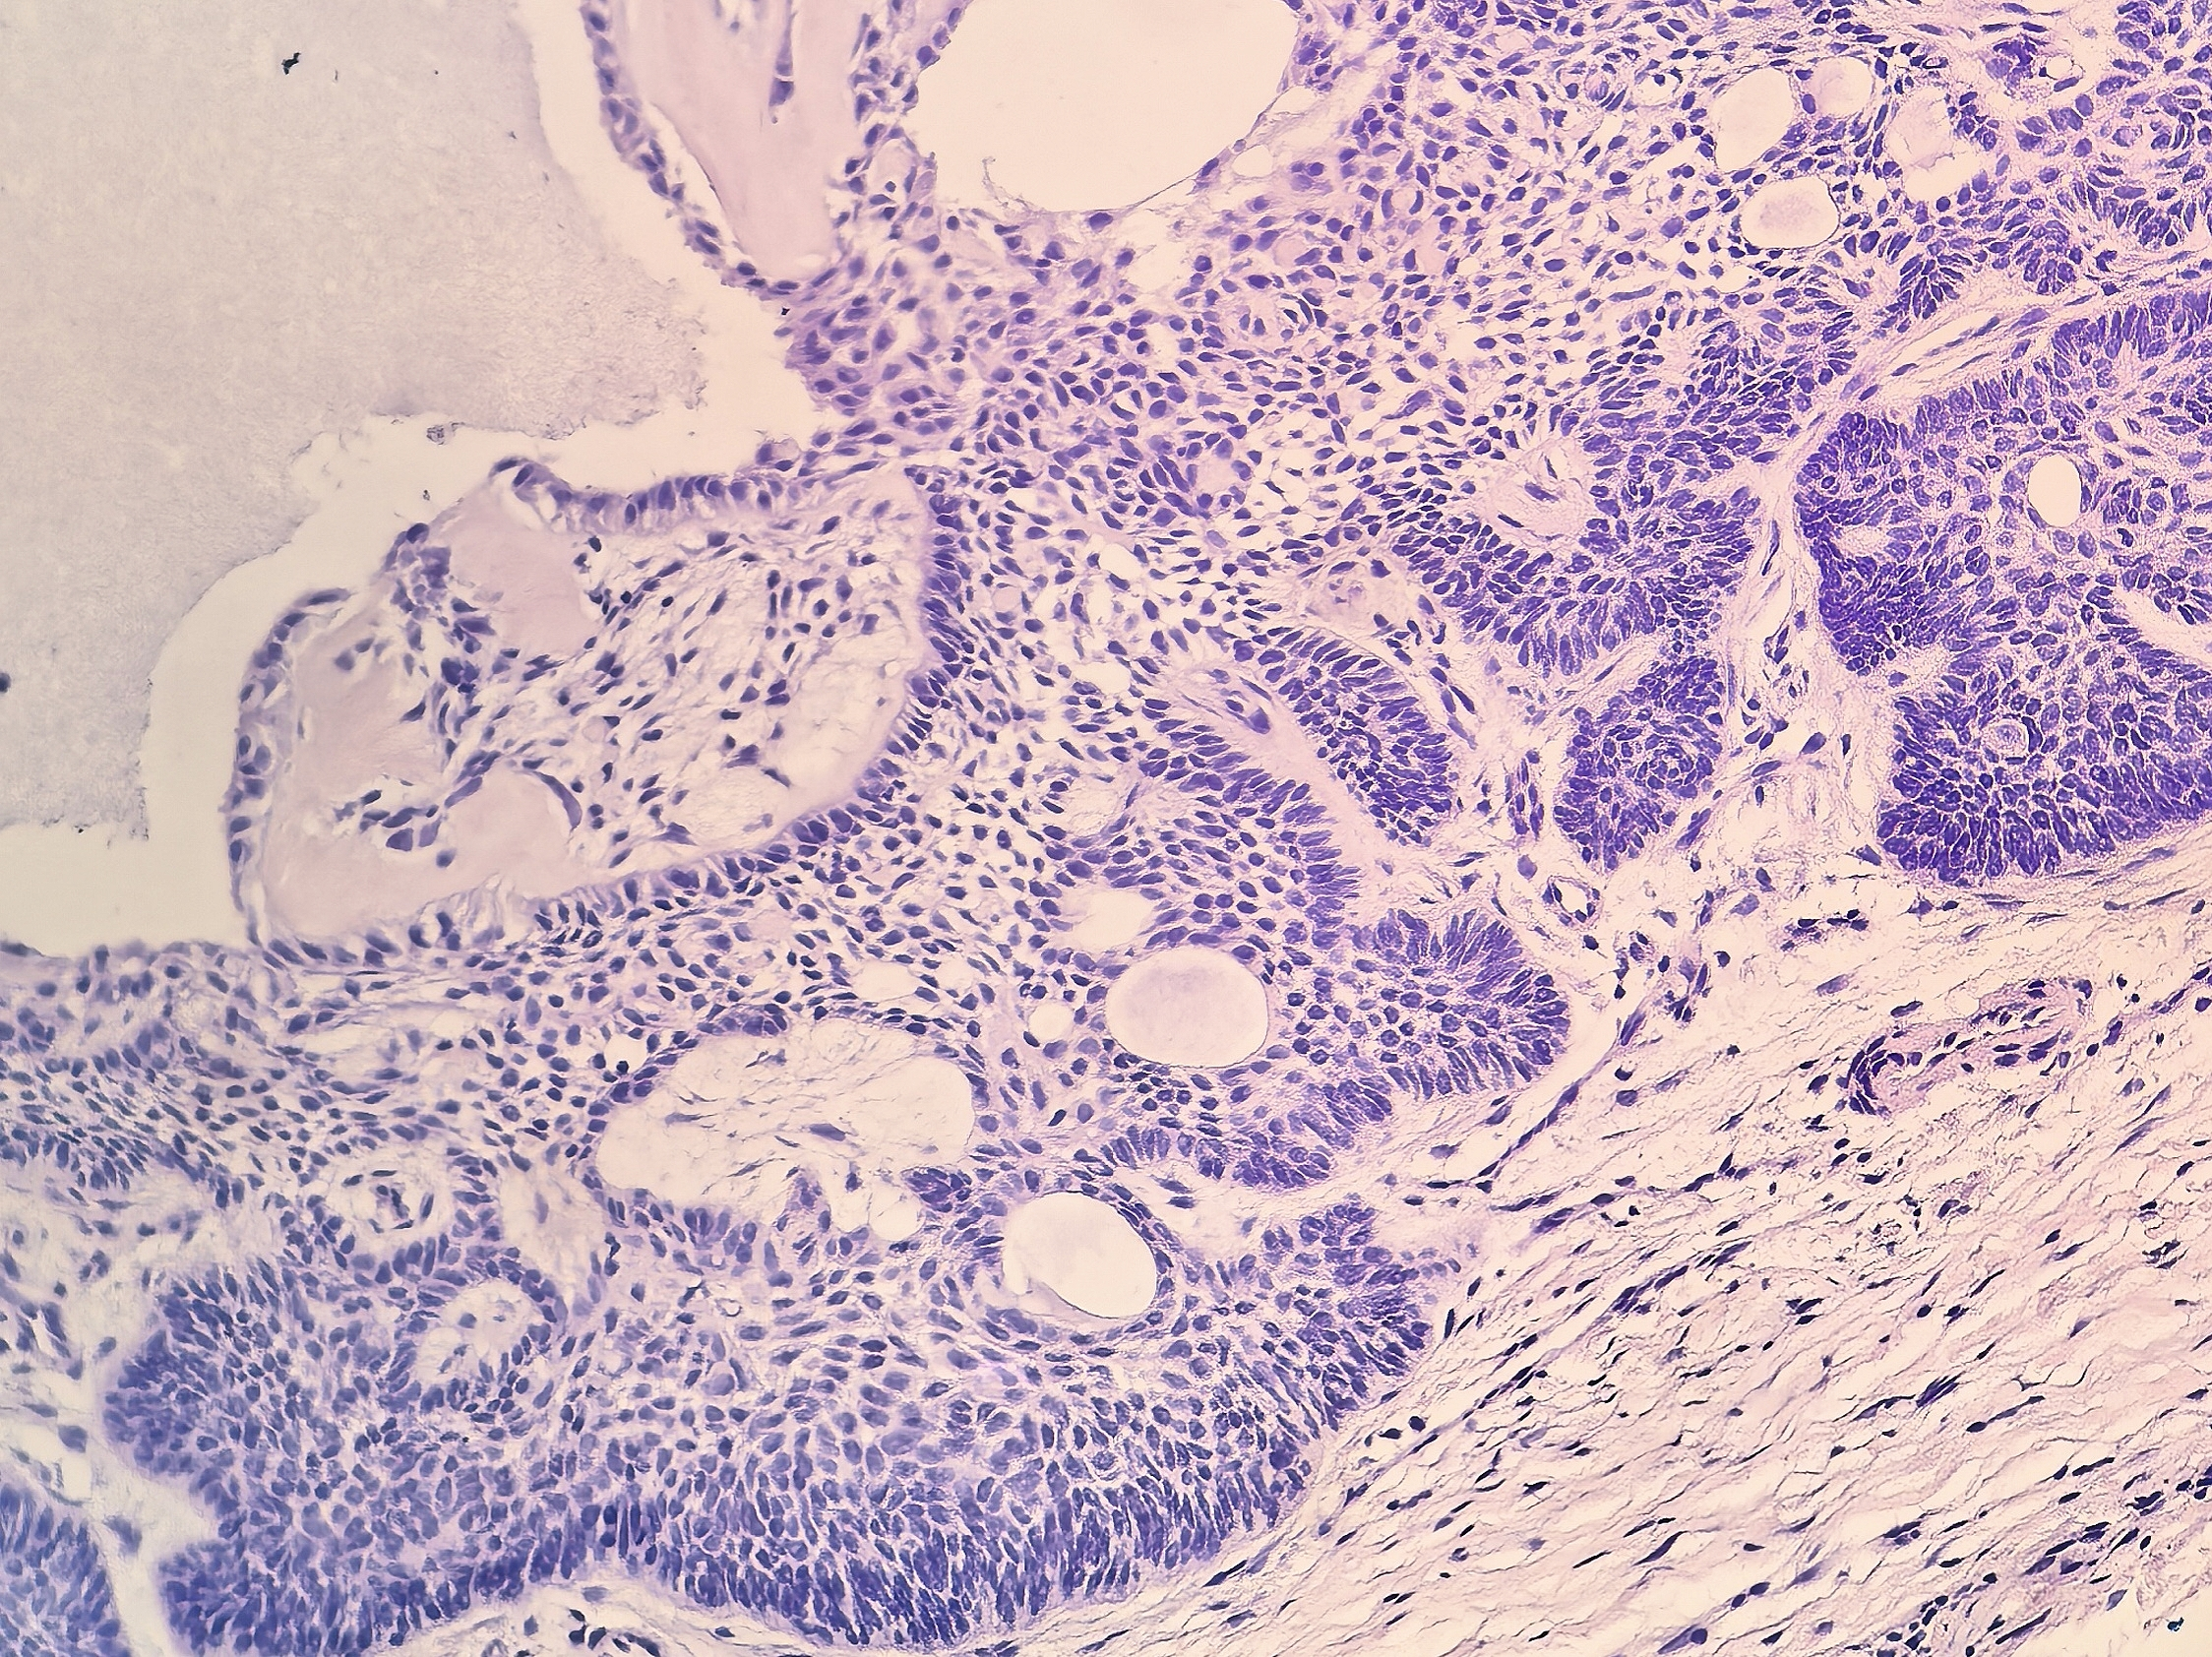

低倍镜下,可见一境界清楚的结节,主要位于真皮内,表面与表皮相连,部分表皮缺失,结节外周部分为蓝染的上皮,中央为粉染的间质,占病变的相当大比例(图1)。

肿瘤对应上方表皮萎缩,真皮内肿瘤细胞呈巢团状,条索状,靠近结节外围分布(图2)。